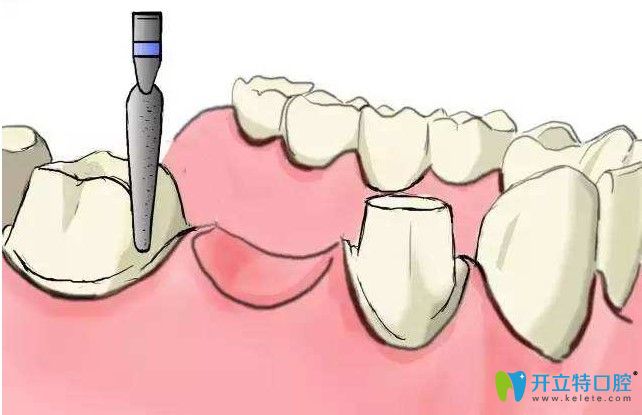

【肖院長(zhǎng)種植牙技術(shù)優(yōu)勢(shì)】:

快:即撥即種、5-10分鐘、一次成型;

準(zhǔn):精準(zhǔn)定位、精準(zhǔn)植入、無(wú)縫對(duì)接;

精:細(xì)節(jié)精微、環(huán)節(jié)精細(xì)、技巧精湛;

微:微小切口、疼痛微小、快速愈合;

恒:一次植入、持久使用、可件一生。